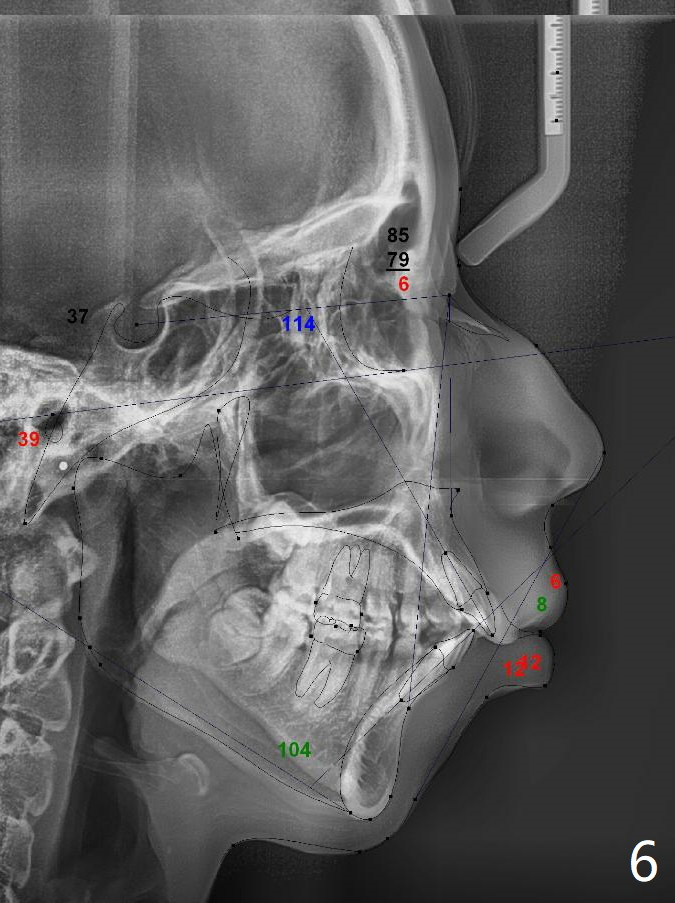

A 15-year-old woman has protrusive lips and retrusive chin (Fig.1-6). Canines and molars have Class I occlusion (Fig.7-9). With 4 bi extraction and 5-7 anchorage (Fig.10-12), 3s will be distalized after 16x16 wires, followed by posted wire retraction of 4 incisors.